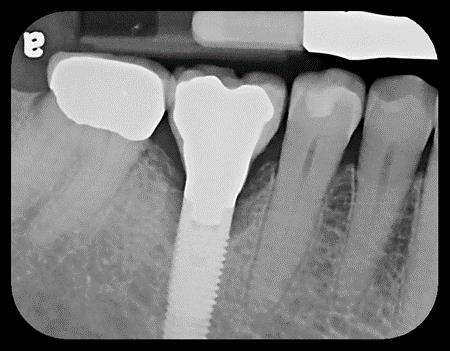

When an implant loses bone on multiple surfaces, it continues to fail and creates a large defect. Ms. R presented with a failing implant having several millimeters of bone loss around it (Fig. 1). The abutment and crown were removed and stored. The implant was detoxified, then grafted with growth-factor-enhanced bone (Fig. 2). After four months, the graft matured and the abutment and crown were reseated (Fig. 3 & 4). Six years later, the bone remains intact around the implant (Fig. 5).

Fig. 2: Bone Graft Repair Complete Fig. 3: Four Months Later, Bone Is Healed Fig. 4: Abutment and Crown Reseated After Healing Fig. 5: Six Years Later, Bone Is Intact